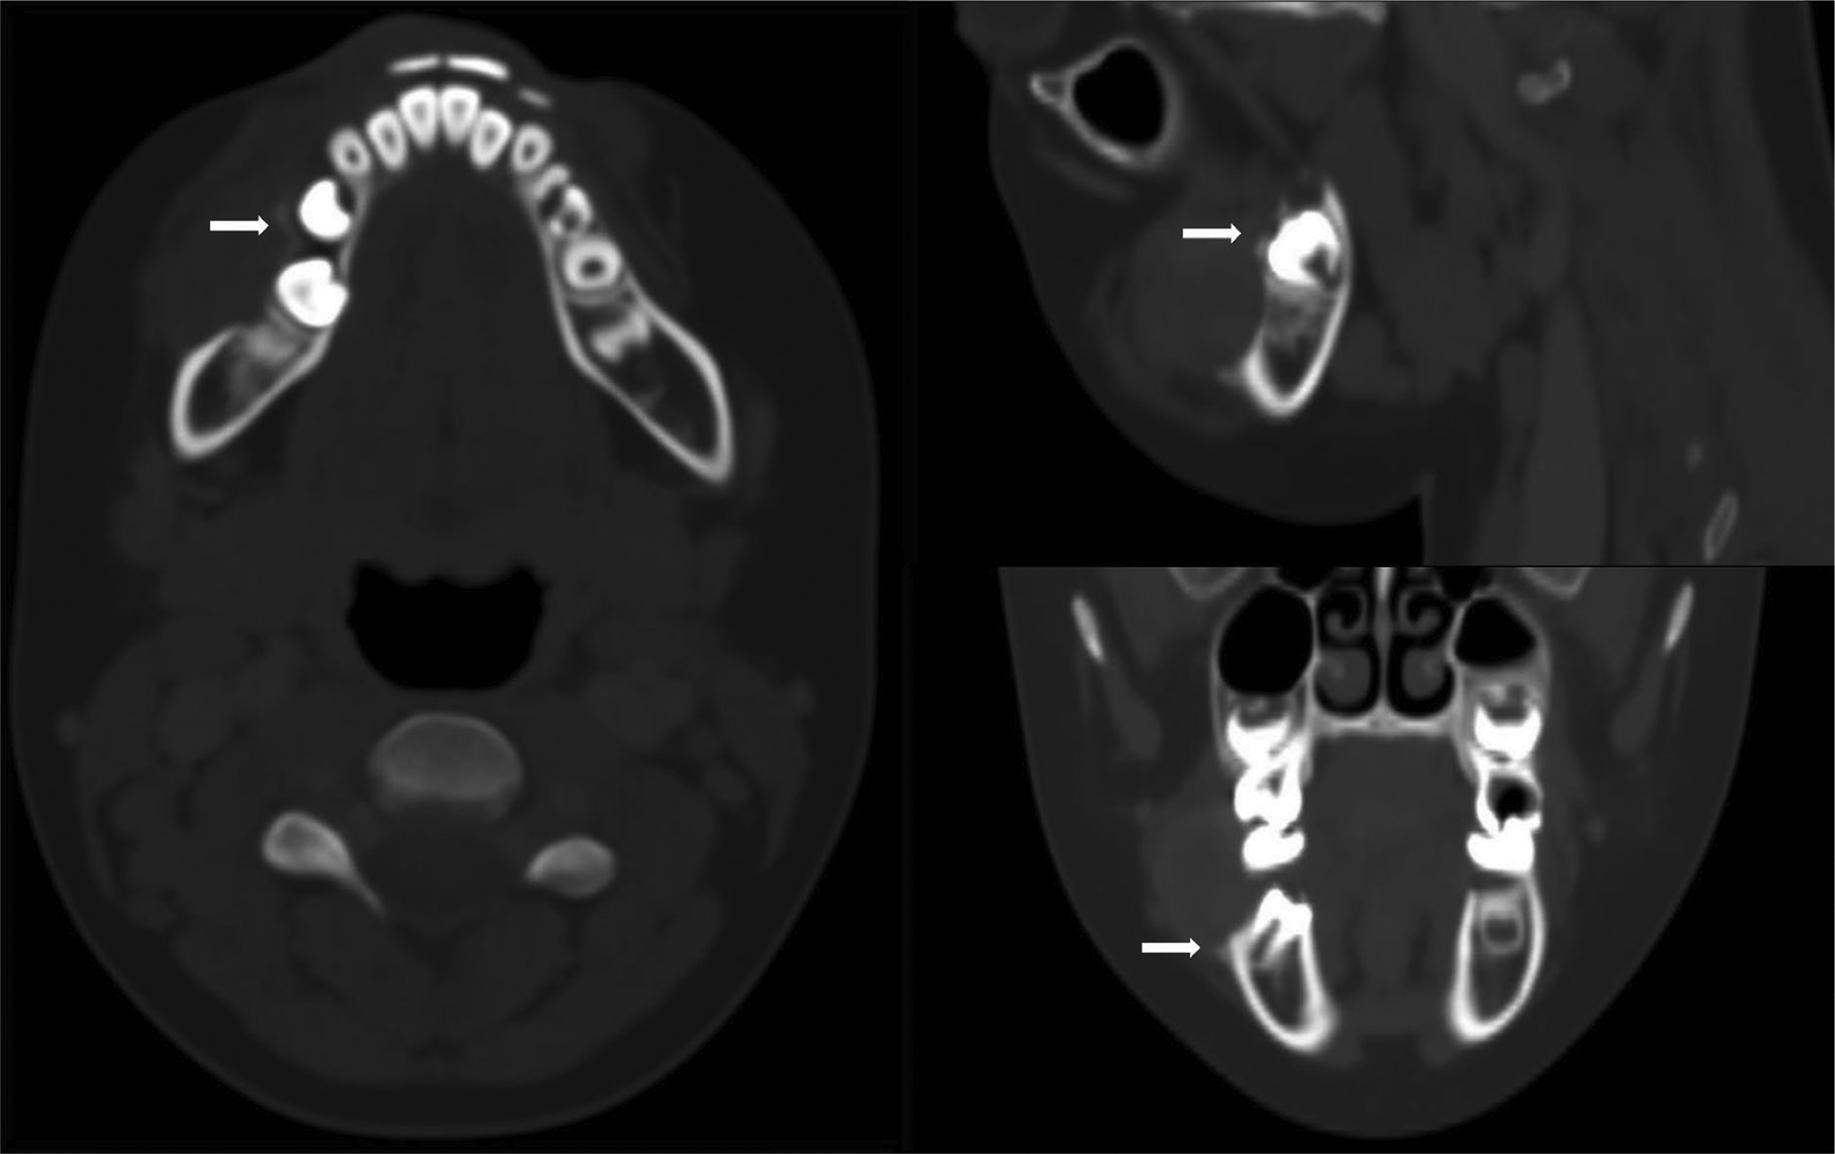

Figure 2

CECT in soft tissue window showing a homogeneously enhancing solid gingival lesion at the buccal aspect (asterisk) causing bulging of the buccinator muscle (white arrowheads).

Figure 3

CECT in bone window revealing superficial bone erosions at outer alveolar ridge (white arrows).

An 8‑year‑old boy with a history of primary second molar extraction in the right mandible presented to the department of maxillofacial surgery with a painful swelling in the right lower jaw. Clinical examination revealed a reddish sessile lesion with an erythematous and ulcerated surface (Figure 1). Contrast‑enhanced computed tomography (CECT) of the right mandibular region demonstrated a non‑calcified, homogeneously enhancing solid lesion, measuring approximately 2 cm, arising from the gingiva at the outer alveolar margin (Figure 2, asterisk) and causing bulging of the buccinator muscle (Figure 2, arrowheads). Bone window reconstructions revealed superficial bone erosion (Figure 3, arrows). Histopathological examination following surgical removal confirmed the diagnosis of peripheral giant cell granuloma (PGCG).

Computed tomography (CT) imaging and OPG typically reveal superficial destruction of the alveolar margin or crest of the interdental bone, characterized by superficial bone erosion (referred to as saucerization or cuffing), newly formed vertical osteoid spicules at the base of the lesion, and widening of the adjacent periodontal space. Cuffing has been reported in nearly one‑third of cases.